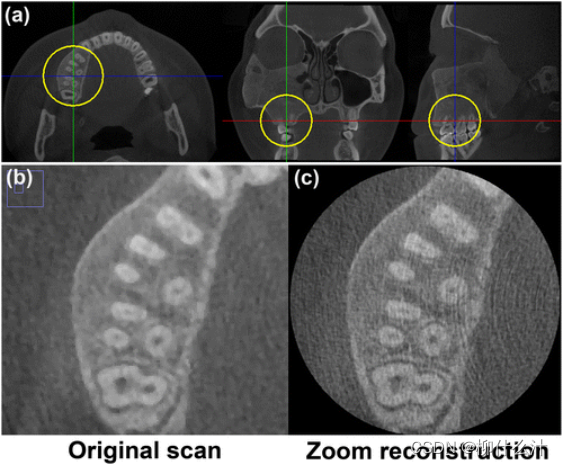

进行变焦是另外一种选择,以突出图像的部分细节。由于文件大小和重建时间的过度增加,大视野CBCT扫描无法在小体素尺寸下重建,之后就引入了变焦重建的规则。由于一些技术限制,大视野扫描不能以其固有的清晰度显示,体素大小成为瓶颈。为了应对这种情况,可以把扫描的焦点缩小选择图像的某个区域,以较小的体素重建该区域,以较高的噪声为代价增加清晰度。这种变焦重建是使用原始数据进行的,避免了在大FOV扫描之外需要高分辨率视图时对病人的额外曝光。

缩放重建。(a) 大视场扫描显示感兴趣区域为4×4×4厘米(圆圈)。(b) 原始扫描的体素大小为0.25毫米。 (c) 缩放重建的体素大小为0.08毫米。